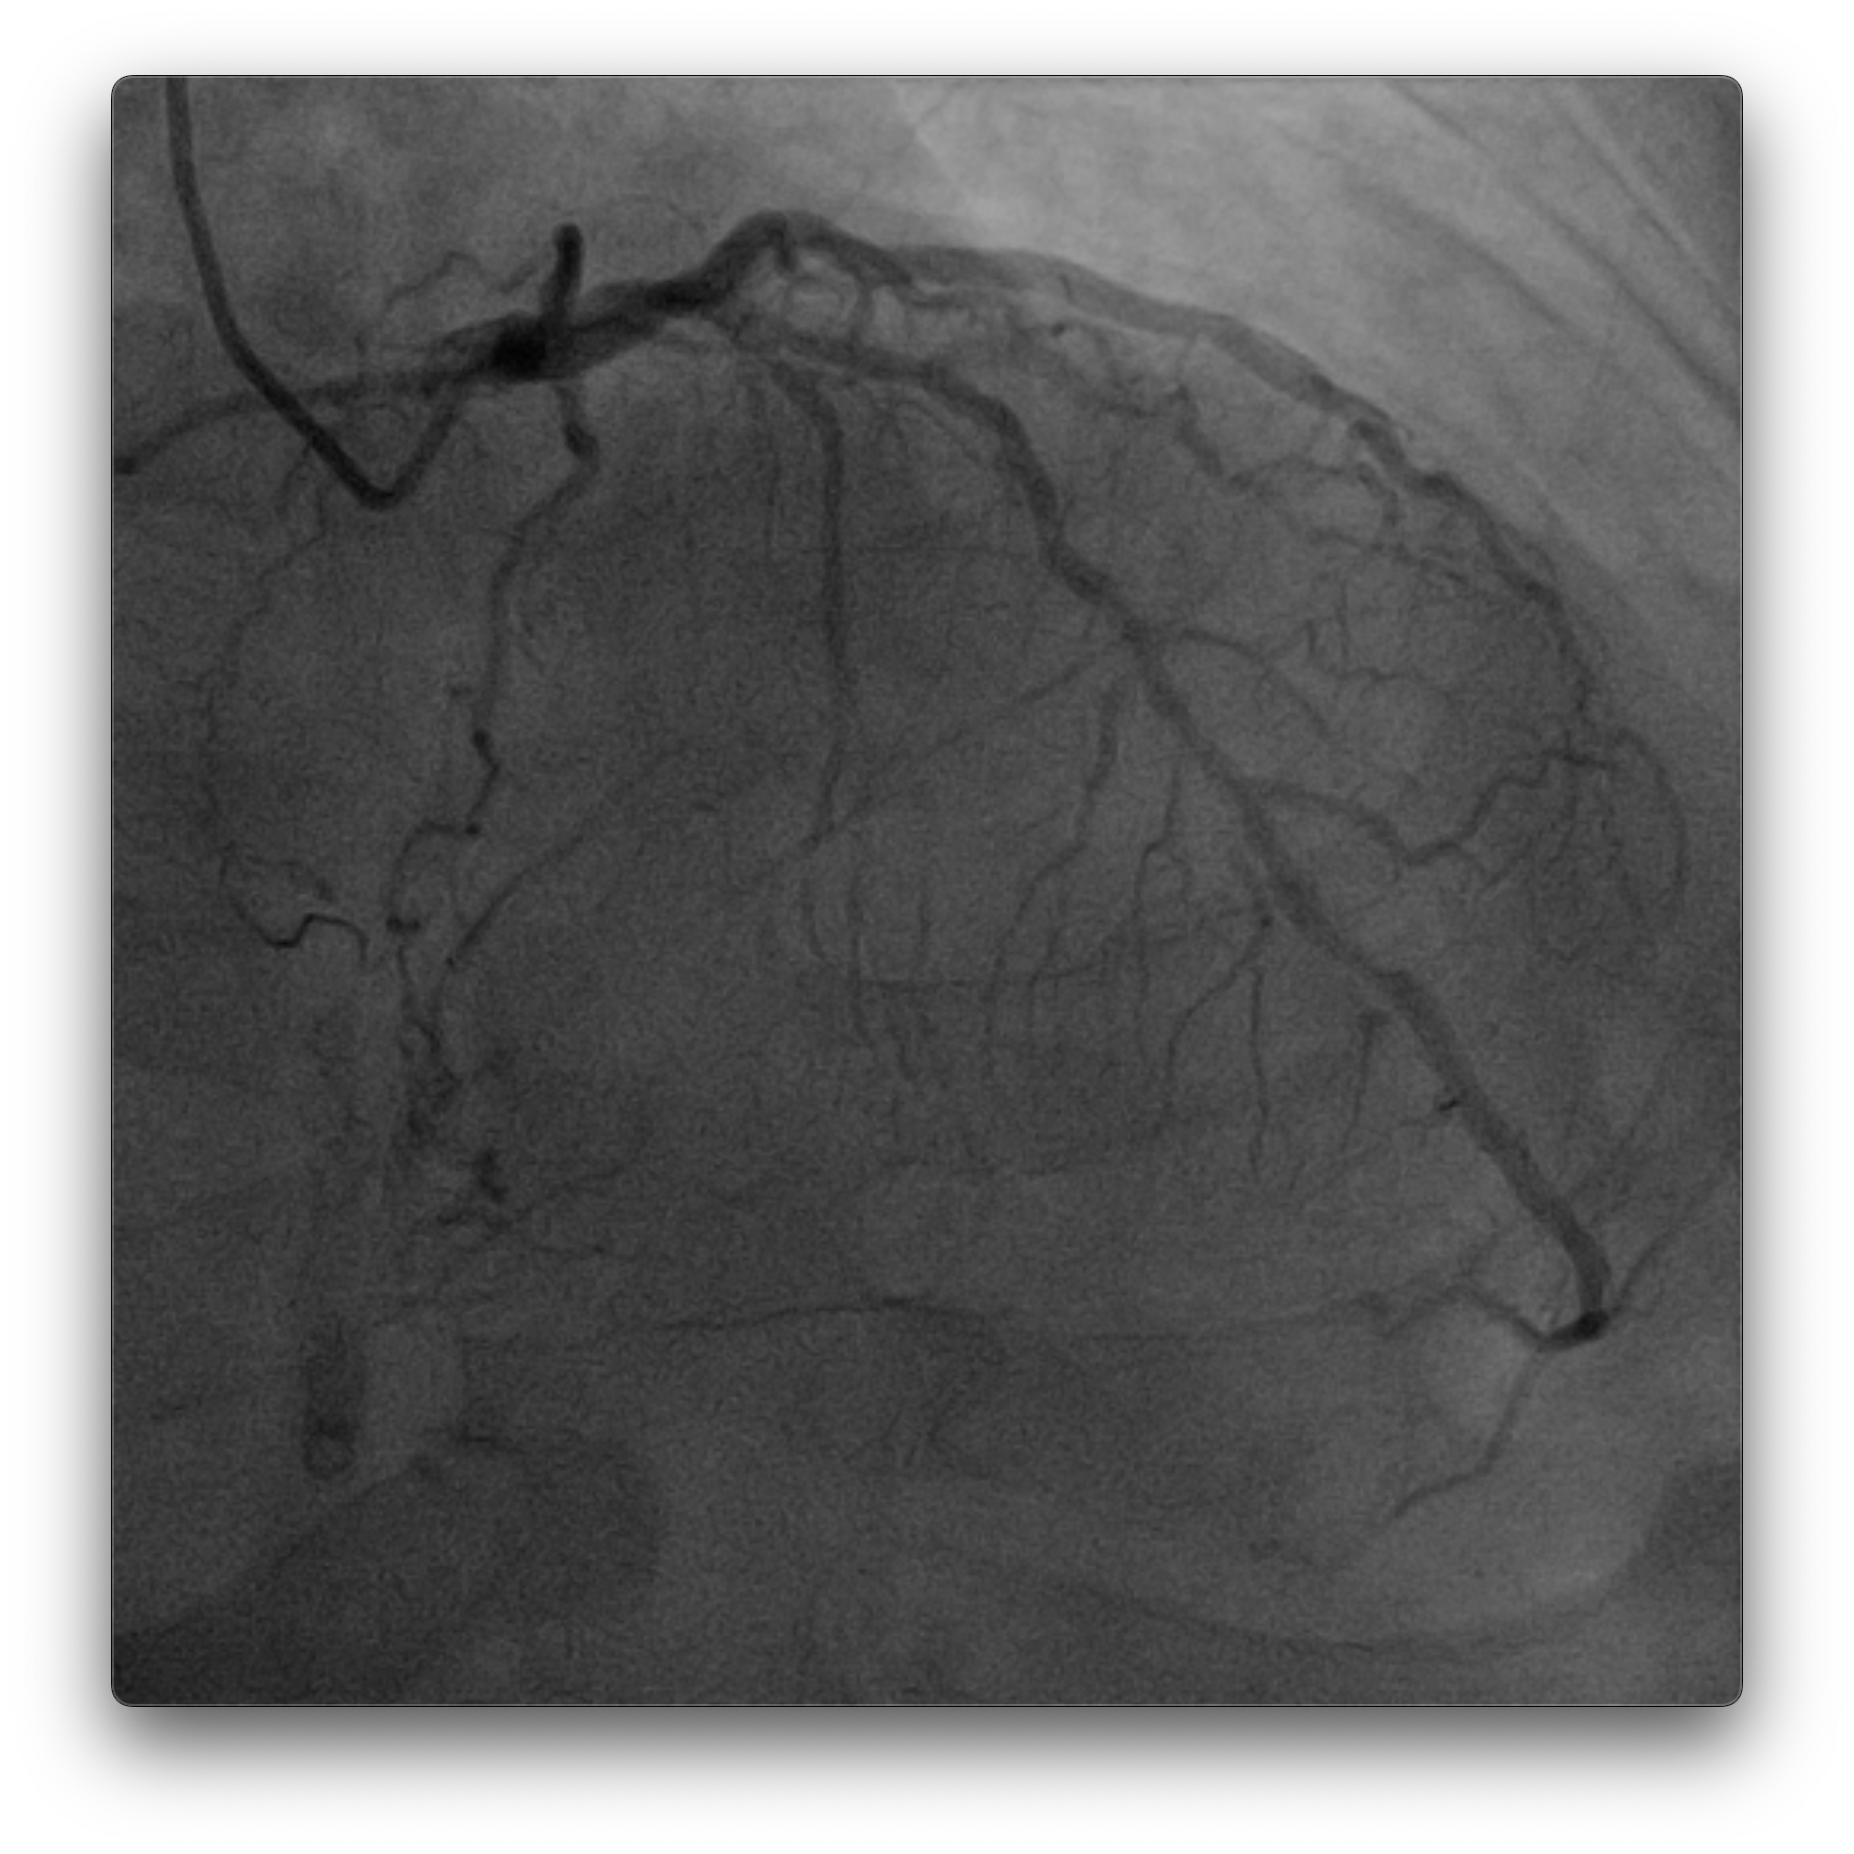

Dominant right coronary artery (RCA) with a heavily calcified, diffusely diseased segment extending from the ostium to the distal portion. The left anterior descending (LAD) and left circumflex (LCx) arteries show irregular but non-significant stenoses

PCI to RCA : Canulation using guiding catheter AL 0.75/7Fr, heparin was administered. Workhorse wire to distal PL. Initial attempt with a 1.5 ¡¿ 15 mm balloon failed to cross the distal lesion and subsequently ruptured. Rotational atherectomy was performed using a 1.5 mm burr at 160–180k rpm with three runs and one polishing pass. A 2.0 ¡¿ 15 mm semi-compliant balloon was then advanced from distal to proximal segments with the assistance of a guide extension catheter.IVUS evaluation demonstrated a 360¡Æ circumferential calcium arc and multiple calcium nodules extending from proximal to distal RCA. Lesion preparation was continued using sequential scoring balloon 2.0 mm and NC 2.5 mm, and cutting balloon 3.0 mm at high pressure. A ¡°dogbone¡± appearance was noted with the cutting balloon at the proximal RCA. An intravascular lithotripsy (IVL) balloon 3.0 mm was then applied to both distal and proximal RCA, delivering a total of 120 pulses (up to 8 atm).Repeat IVUS confirmed adequate calcium modification and optimal lesion preparation. Three overlapping drug-eluting stents (DES) were deployed: 3.0 ¡¿ 38 mm (distal–mid RCA), 3.5 ¡¿ 32 mm (mid RCA), and 4.0 ¡¿ 22 mm (ostial–proximal RCA), followed by sequential post-dilatation up to 4.0 mm. Final IVUS confirmed good stent apposition and expansion, with a minimal stent area of 6.36 mm©÷ at the distal RCA. TIMI 3 flow was achieved. Total contrast volume: 160 mL, Fluoroscopy time: 01:09:34 minutes, DAP: 232 Gy¡¤cm©÷